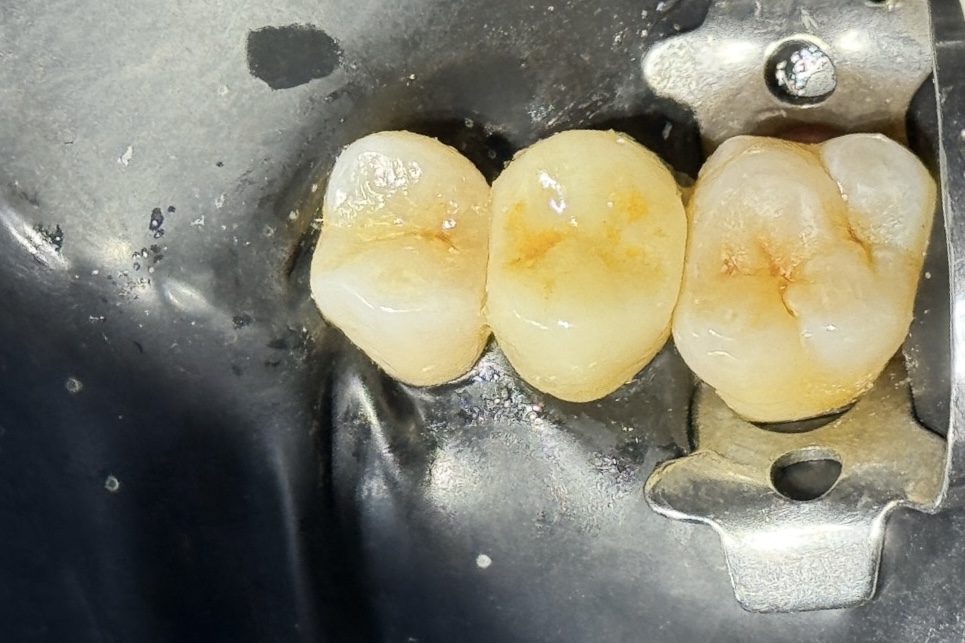

Final restorations exhibited perfect proximal contact, smooth occlusal transition, and natural optical blending across the quadrant (Fig 8). At 3-month review, both teeth remained symptom-free with stable margins and ideal occlusion.

- Fig 8: Post-operative quadrant result showing functional and esthetic integration.

This quadrant restorative workflow successfully rehabilitated both posterior teeth in a single session using biomimetic layering, isolation control, and fiber-reinforced reinforcement. The combination of GC EverX Flow and Tokuyama Estelite Sigma Quick achieved anatomical, functional, and esthetic harmony.